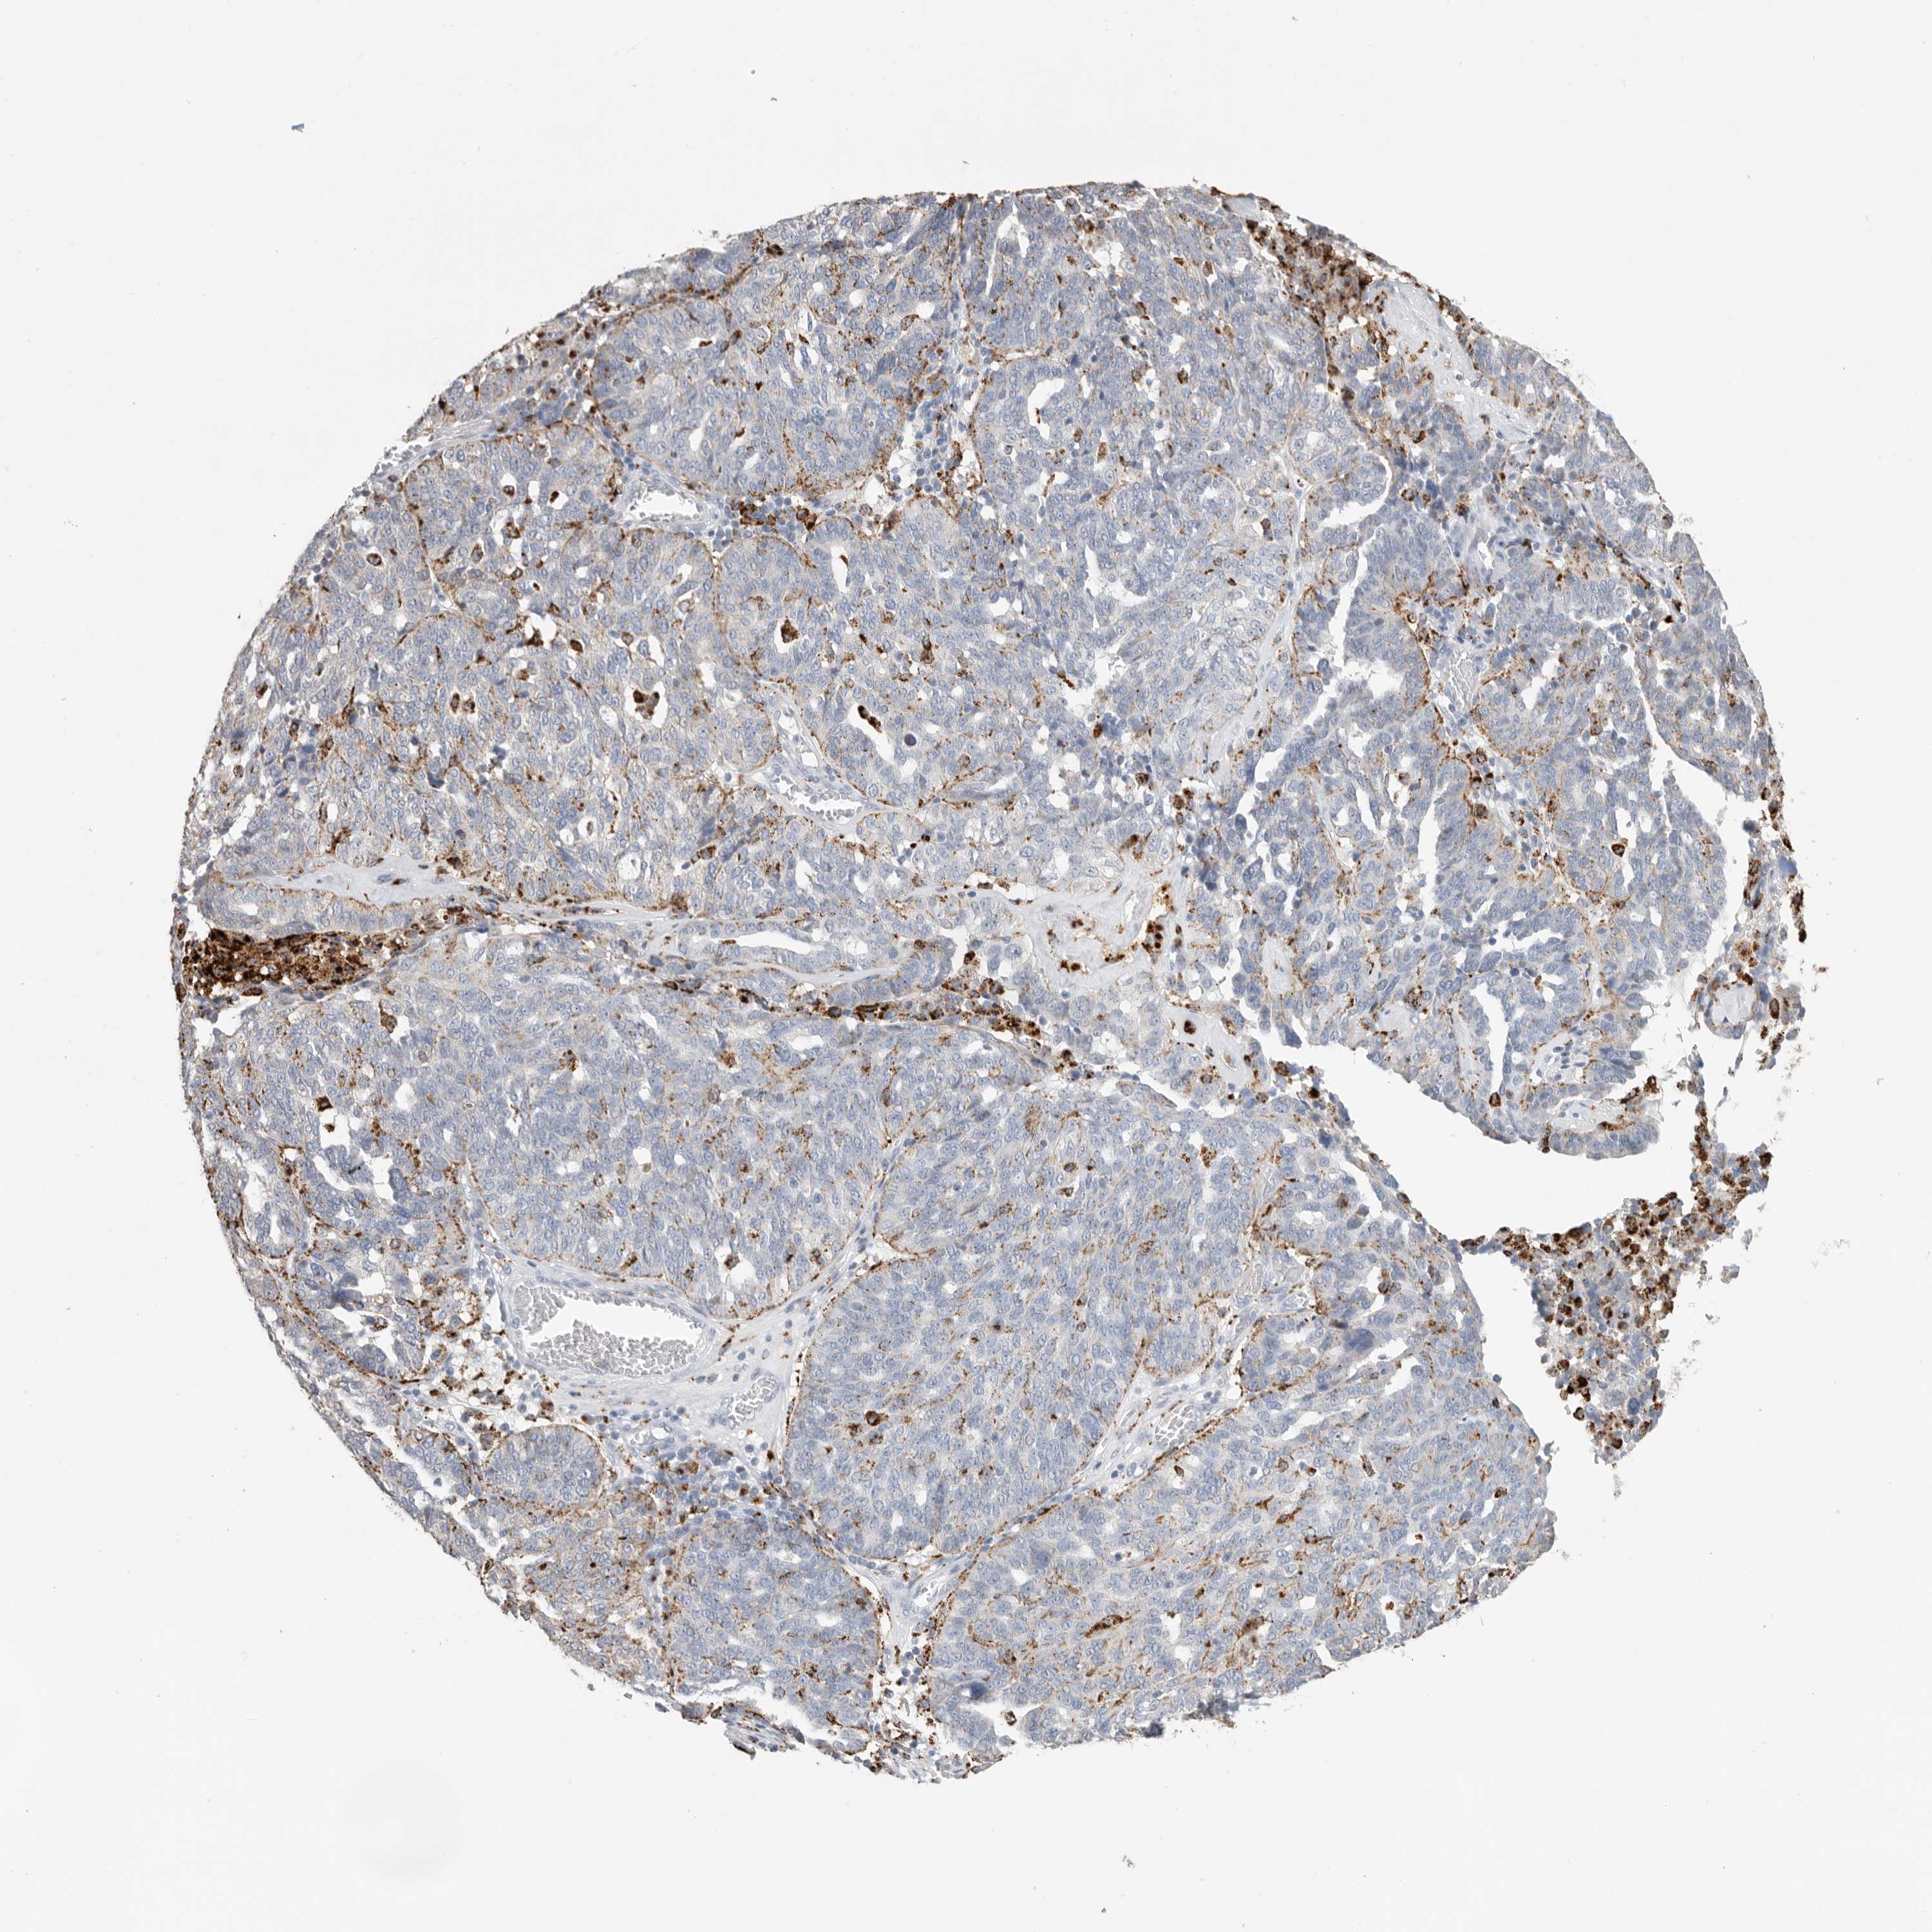

OVARIAN CANCER - Protein expressioni

A mouse-over function shows sample information and annotation data. Click on an image to view it in a full screen mode. Samples can be filtered based on level of antibody staining by selecting one or several of the following categories: high, medium, low and not detected. The assay and annotation is described here.

Note that samples used for immunohistochemistry by the Human Protein Atlas do not correspond to samples in the TCGA dataset.

Antibody stainingi

Antibody staining in the annotated cell types in the current human tissue is reported as not detected, low, medium, or high, based on conventional immunohistochemistry profiling in selected tissues. This score is based on the combination of the staining intensity and fraction of stained cells.

Each image is clickable and will lead to virtual microscopy that enables deeper exploration of all samples and also displays staining intensity scores, fraction scores and subcellular localization as well as patient and tissue information for each sample.

Antibody HPA025226

Antibody CAB019296